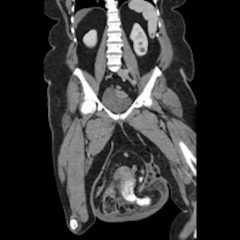

Magnetic resonance imaging (MRI) showed an “expansile, destructive solid and cystic mass with aggressive…characteristics…” (see images). Tissue biopsy confirmed a giant cell tumor arising from the bone. The patient underwent a debulking procedure, and later a distal amputation. Follow-up on pathology showed negative margins.

The best imaging study is MRI, to assess for bony and tissue involvement and surgical approach. Computed tomography may be used; however, it doesn’t delineate the soft tissue and bony connections as well. Standard oncology labs should be drawn as well, including: CBC with differential, LDH, uric acid, CMP, ESR. The growth of the tumor is insidious and therefore imaging should be done based on clinical concern. In the ED setting, if close follow up can be ensured, imaging can be done as an out-patient. Annual surveillance is recommended for at least five years in most patients, even after total resection, according to some studies.3